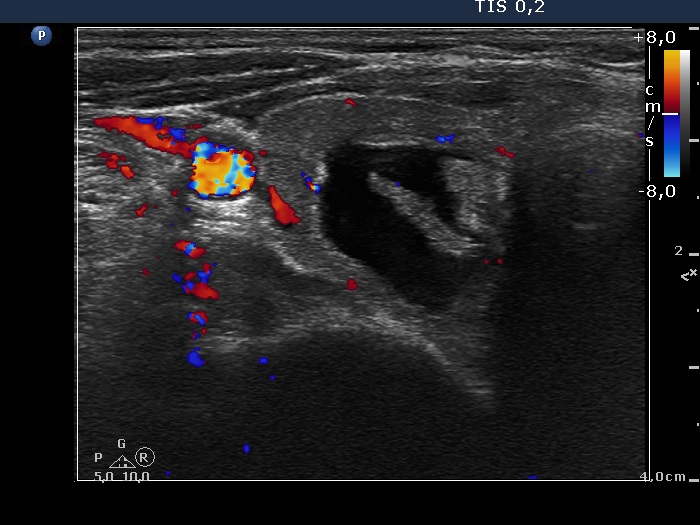

Ultrasonography. The thyroid was echonormal. There was moderately hypoechogenic nodule with blurred borders in the central part of the right lobe. A cystic nodule having echonormal solid part was found in the lower pole of the right lobe. The left lobe also has a cystic nodule.